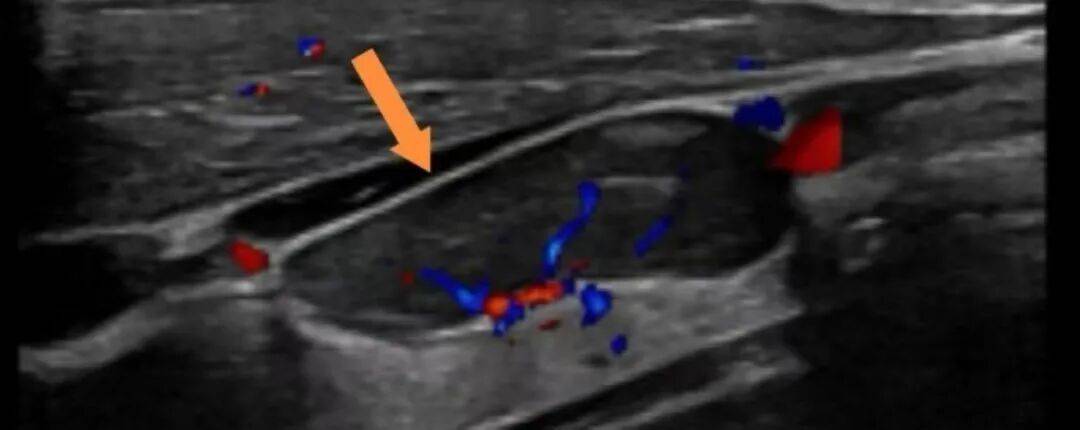

挂职期间,白熠洲曾接诊一位三阴性乳腺癌患者,新辅助化疗无效肿瘤疯长至12厘米,仔细研判后摆在面前的方案只剩下一种——手术搏一线生机。然而极度虚弱的患者与罕见的肿瘤类型,使得手术风险极高。白熠洲快速启动了乳腺癌多学科诊疗(MDT)机制,肿瘤内科、麻醉科、影像科、病理科、输血科悉数到场,团队逐项分析,针对每一个难点制定了应对措施,千方百计创造手术机会。白熠洲又请北京清华长庚医院、北京肿瘤医院专家为方案远程“把脉”。在多学科团队的守护下,患者历经休克抢救、损伤控制、改善营养状态和稳定内环境、精准手术与系统康复等一系列环节后,最终手术顺利完成。术后14天患者复诊时,体重已经增长了6kg之多。

从一个不典型肿瘤的诊断 透视多学科诊疗的默契